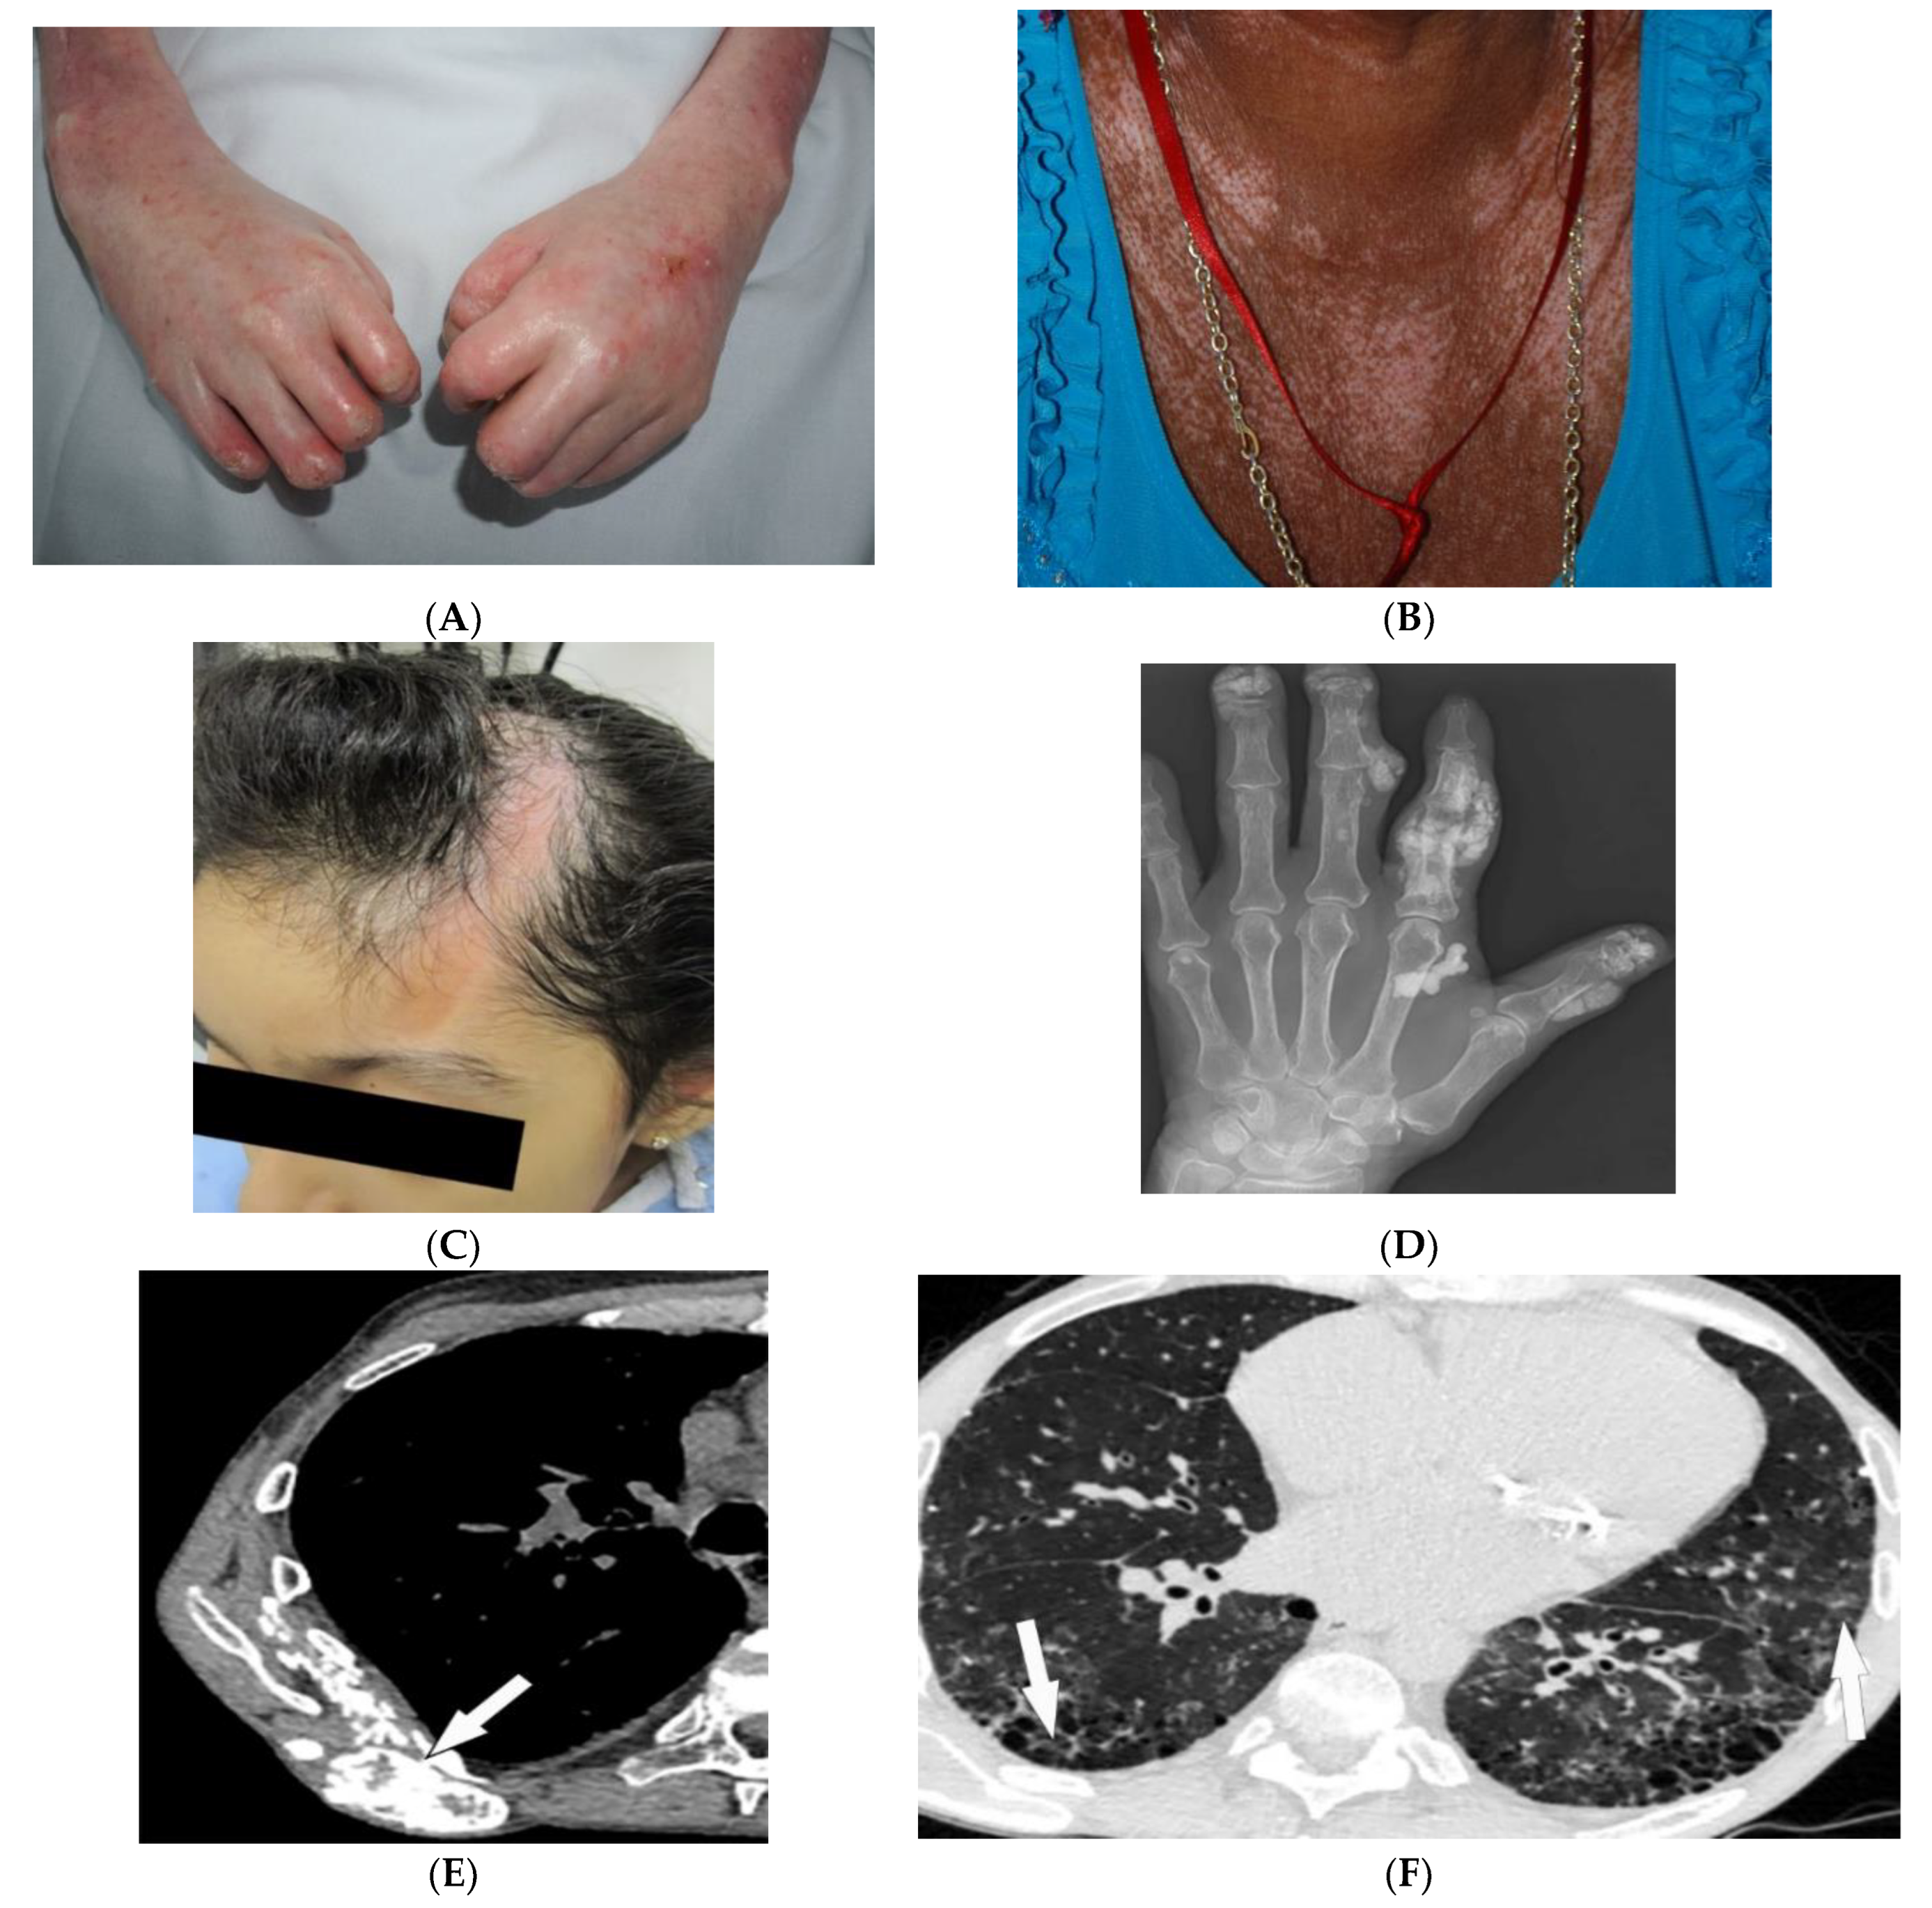

2.1. Dermatomyositis

| Dermatomyositis | Atrophic dermal papules of dermatomyositis (Gottron papules), Gottron sign, heliotrope rash, V sign, shawl sign, calcinosis cutis Proximal nailfold erythema, capillary loop dilation and dropout, ragged cuticles Esophageal dysmotility Myositis ILD Malignancy | Calcinosis cutis Feathery edema-like SI of the muscles NSIP, OP, UIP |